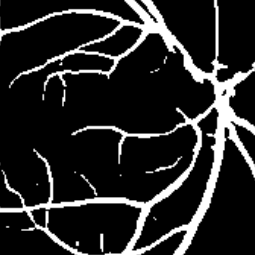

Semantic segmentation of blood vessels is an important task in medical image analysis, but its progress is often hindered by the scarcity of large annotated datasets and the poor generalization of models across different imaging modalities. A key aspect is the tendency of Convolutional Neural Networks (CNNs) to learn texture-based features, which limits their performance when applied to new domains with different visual characteristics. We hypothesize that leveraging geometric priors of vessel shapes, such as their tubular and branching nature, can lead to more robust and data-efficient models. To investigate this, we introduce VessShape, a methodology for generating large-scale 2D synthetic datasets designed to instill a shape bias in segmentation models. VessShape images contain procedurally generated tubular geometries combined with a wide variety of foreground and background textures, encouraging models to learn shape cues rather than textures. We demonstrate that a model pre-trained on VessShape images achieves strong few-shot segmentation performance on two real-world datasets from different domains, requiring only four to ten samples for fine-tuning. Furthermore, the model exhibits notable zero-shot capabilities, effectively segmenting vessels in unseen domains without any target-specific training. Our results indicate that pre-training with a strong shape bias can be an effective strategy to overcome data scarcity and improve model generalization in blood vessel segmentation.